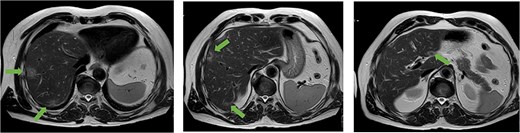

A 56-year-old man, who had undergone anterior rectal resection for upper rectal carcinoma 9 months prior, presented with ˃20 synchronous liver metastases involving both hepatic lobes (Fig. 1).

Axial MRI slices obtained preoperatively showing bilobar colorectal liver metastases. Key lesions are marked with arrows.